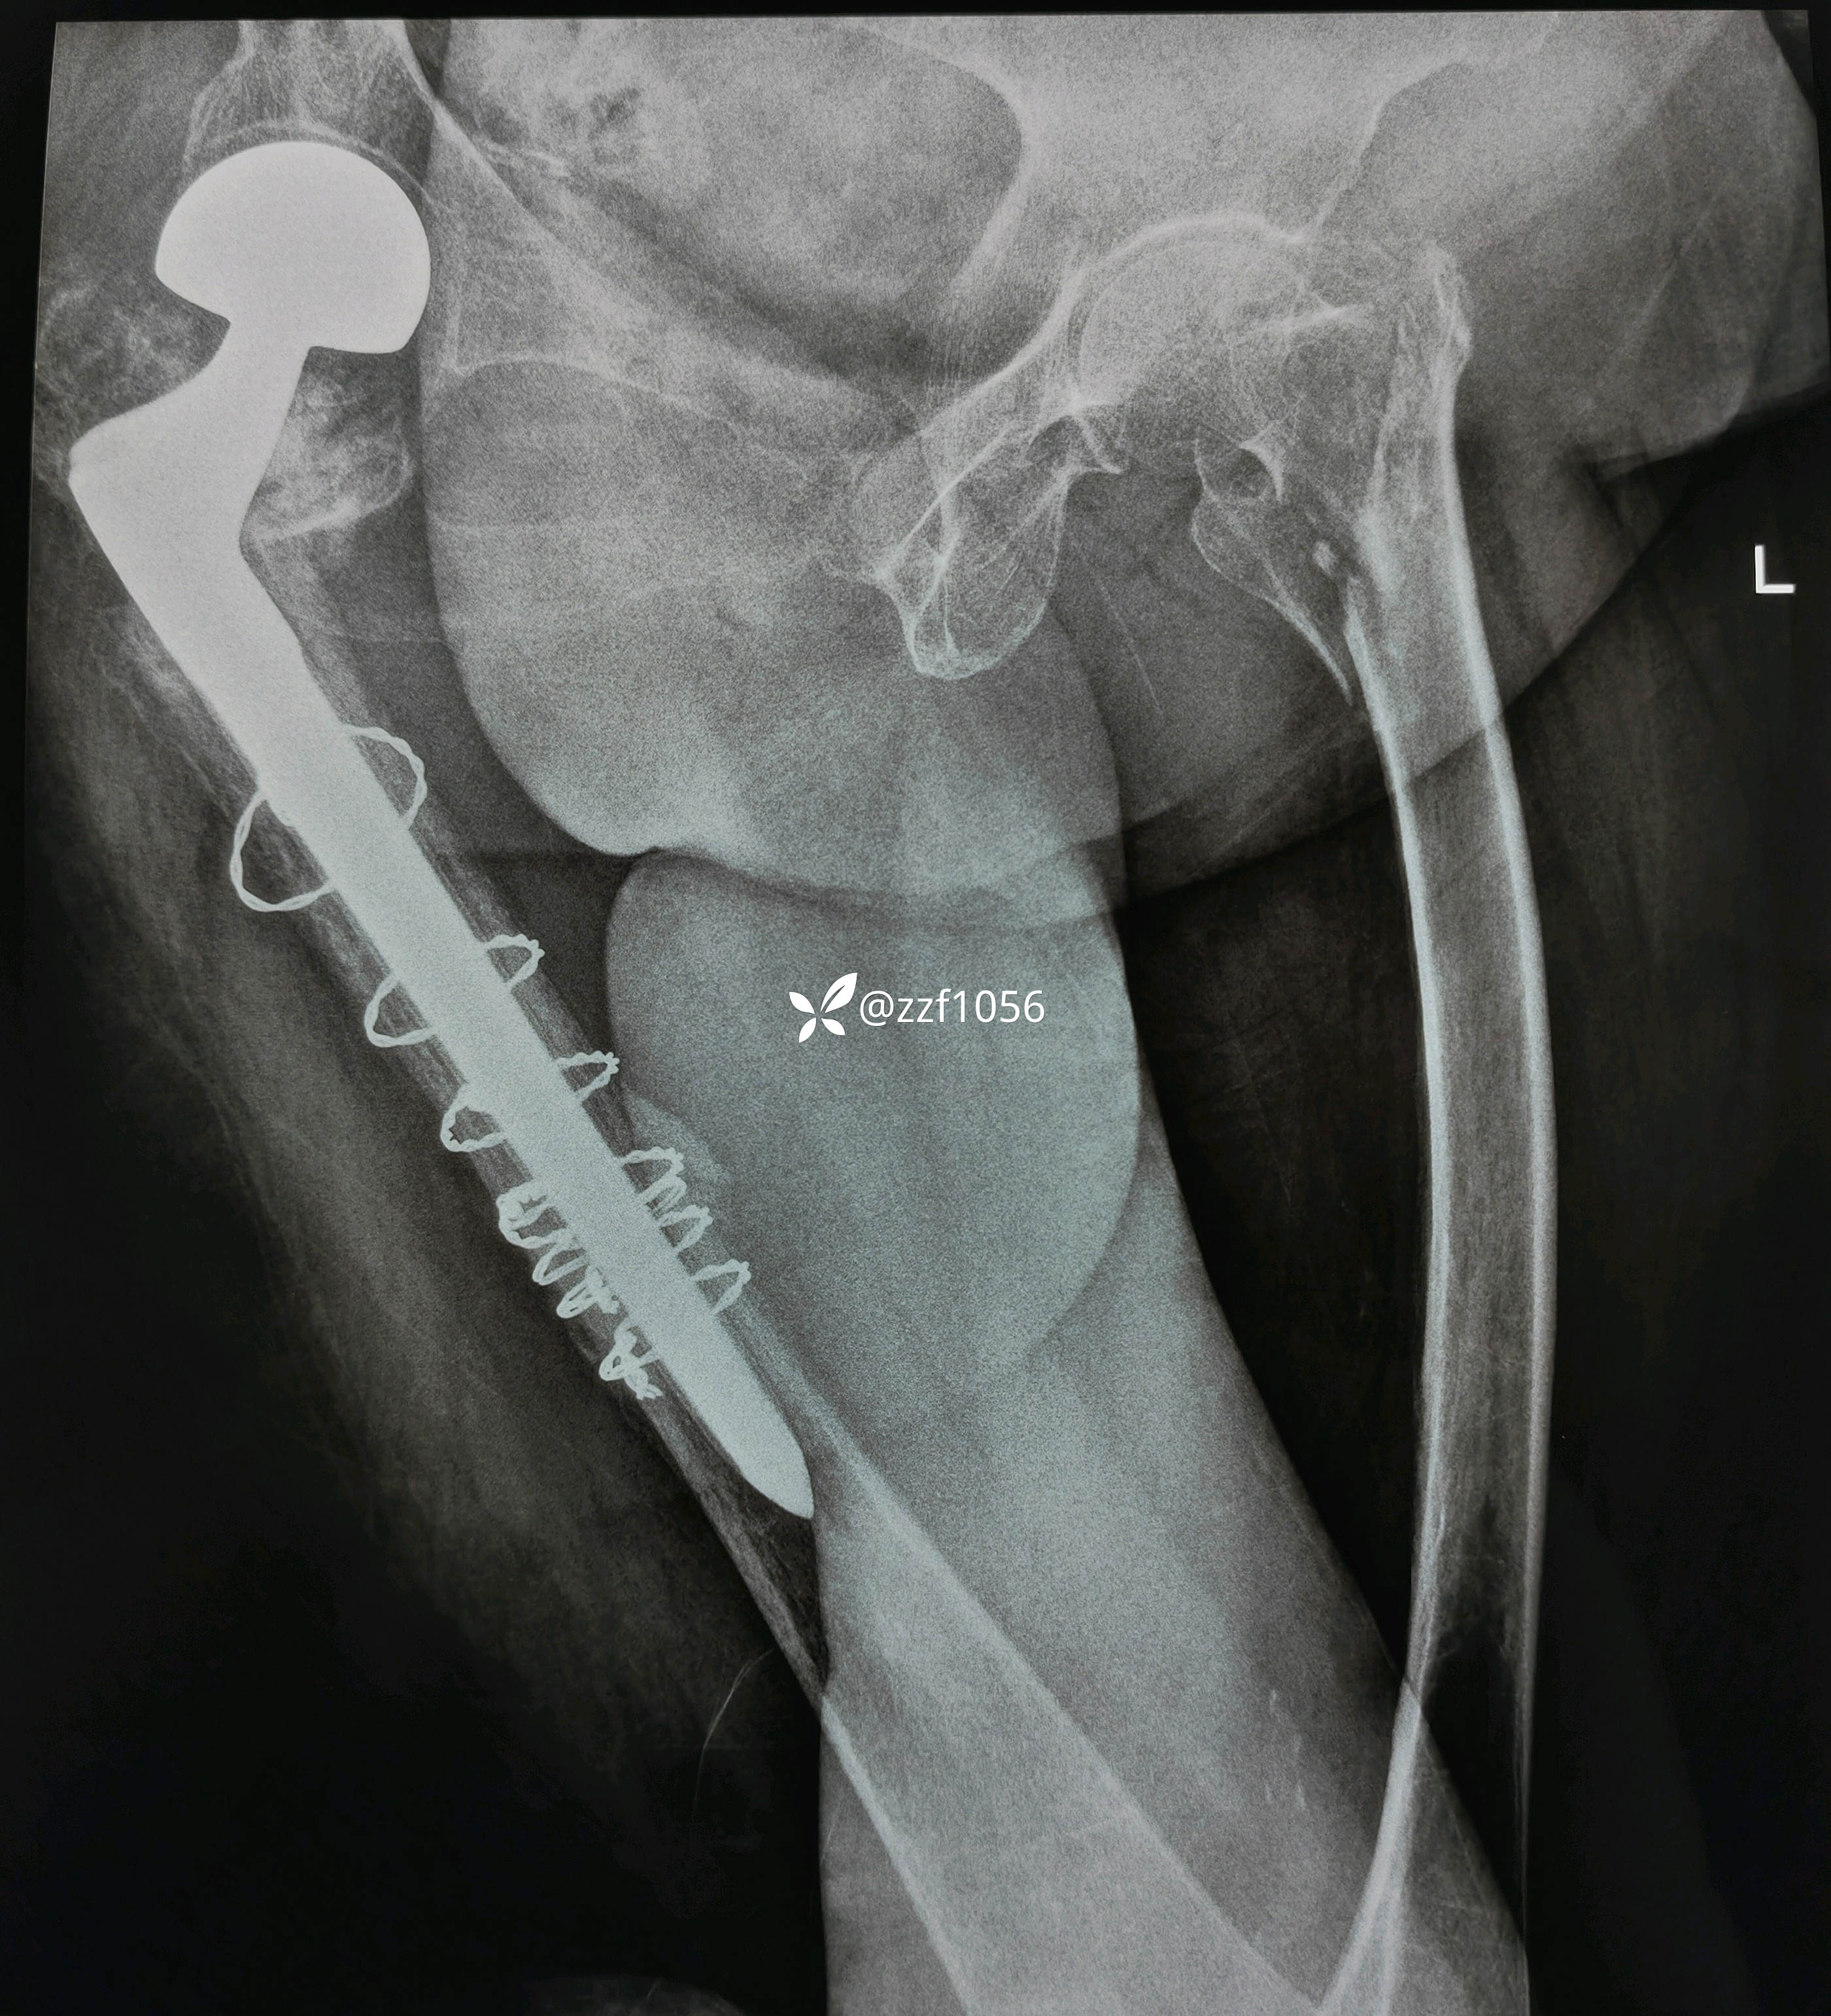

祸不单行,pfna失效,改关节置换术中股骨干再骨折,病房休克抢救,时隔四个月再次骨折

术中去除内固定顺利,使用瓦格纳柄,术中出现插曲,出血量多和干部骨折,多处捆扎,全髋改半髋下台,😰虐心,懂得都懂

行走三个月康复良好,奈何再次摔伤,导致左侧转子间再骨折,A2.3型